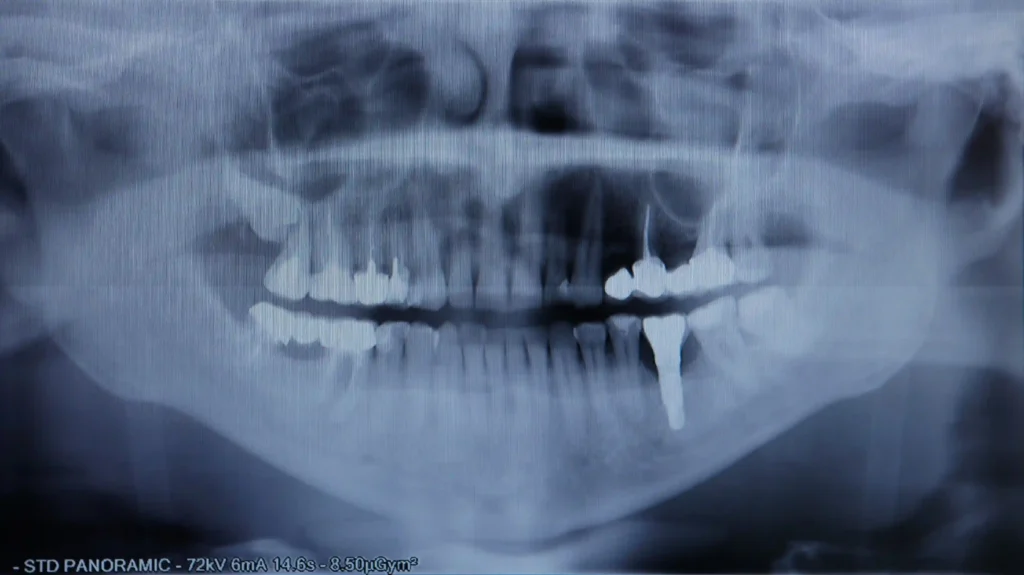

O protocolo Dentes no Dia é uma solução revolucionária que permite ao paciente sair da clínica no mesmo dia da colocação dos implantes com dentes fixos e funcionais. Através de um estudo prévio detalhado — incluindo tomografia computorizada e planeamento digital — a cirurgia é realizada com grande precisão e segurança.

Este tratamento é indicado para pacientes que perderam todos ou a maioria dos dentes e procuram uma solução rápida, confortável e esteticamente perfeita. Com acompanhamento pós-operatório dedicado, os resultados são transformadores: recupera-se a função, a estética e, acima de tudo, a qualidade de vida.